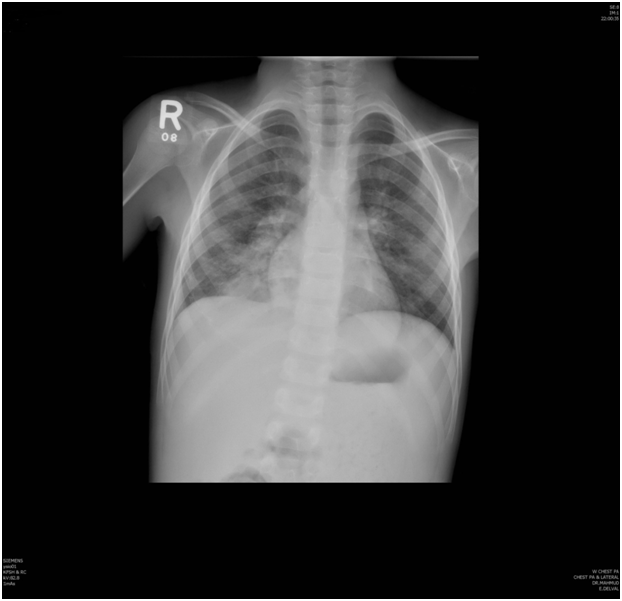

Chest radiography showed right lower and middle lobe infiltrates (Figure 1). Because of these findings our pediatric pulmonary service was consulted.

Figure 1 Chest radiography showed right lower and middle lobe infiltrates.